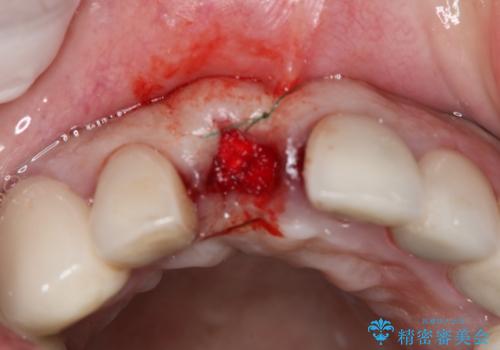

- 事故による外傷で前歯に歯根が真っ二つに折れてしまい、保存不可能となってしまった部分にインプラント治療を計画しました。

患者様のご要望もあり、審美性の確保ができる抜歯早期埋入→埋入後即時荷重という手術法を取りました。

近年、インプラントの素材や手術法の研究が進み、保存不可能となった歯牙に対して抜歯してすぐインプラントを埋入し、さらに直後から仮歯がを入れ噛むことができる【抜歯即時埋入】【即時荷重】という技法が確立されました。